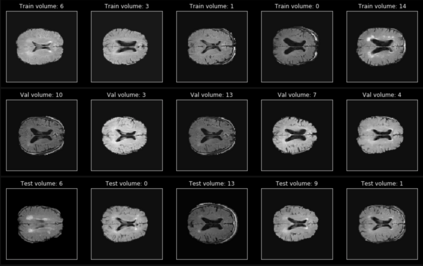

In recent years, data-driven machine learning (ML) methods have revolutionized the computer vision community by providing novel efficient solutions to many unsolved (medical) image analysis problems. However, due to the increasing privacy concerns and data fragmentation on many different sites, existing medical data are not fully utilized, thus limiting the potential of ML. Federated learning (FL) enables multiple parties to collaboratively train a ML model without exchanging local data. However, data heterogeneity (non-IID) among the distributed clients is yet a challenge. To this end, we propose a novel federated method, denoted Federated Disentanglement (FedDis), to disentangle the parameter space into shape and appearance, and only share the shape parameter with the clients. FedDis is based on the assumption that the anatomical structure in brain MRI images is similar across multiple institutions, and sharing the shape knowledge would be beneficial in anomaly detection. In this paper, we leverage healthy brain scans of 623 subjects from multiple sites with real data (OASIS, ADNI) in a privacy-preserving fashion to learn a model of normal anatomy, that allows to segment abnormal structures. We demonstrate a superior performance of FedDis on real pathological databases containing 109 subjects; two publicly available MS Lesions (MSLUB, MSISBI), and an in-house database with MS and Glioblastoma (MSI and GBI). FedDis achieved an average dice performance of 0.38, outperforming the state-of-the-art (SOTA) auto-encoder by 42% and the SOTA federated method by 11%. Further, we illustrate that FedDis learns a shape embedding that is orthogonal to the appearance and consistent under different intensity augmentations.